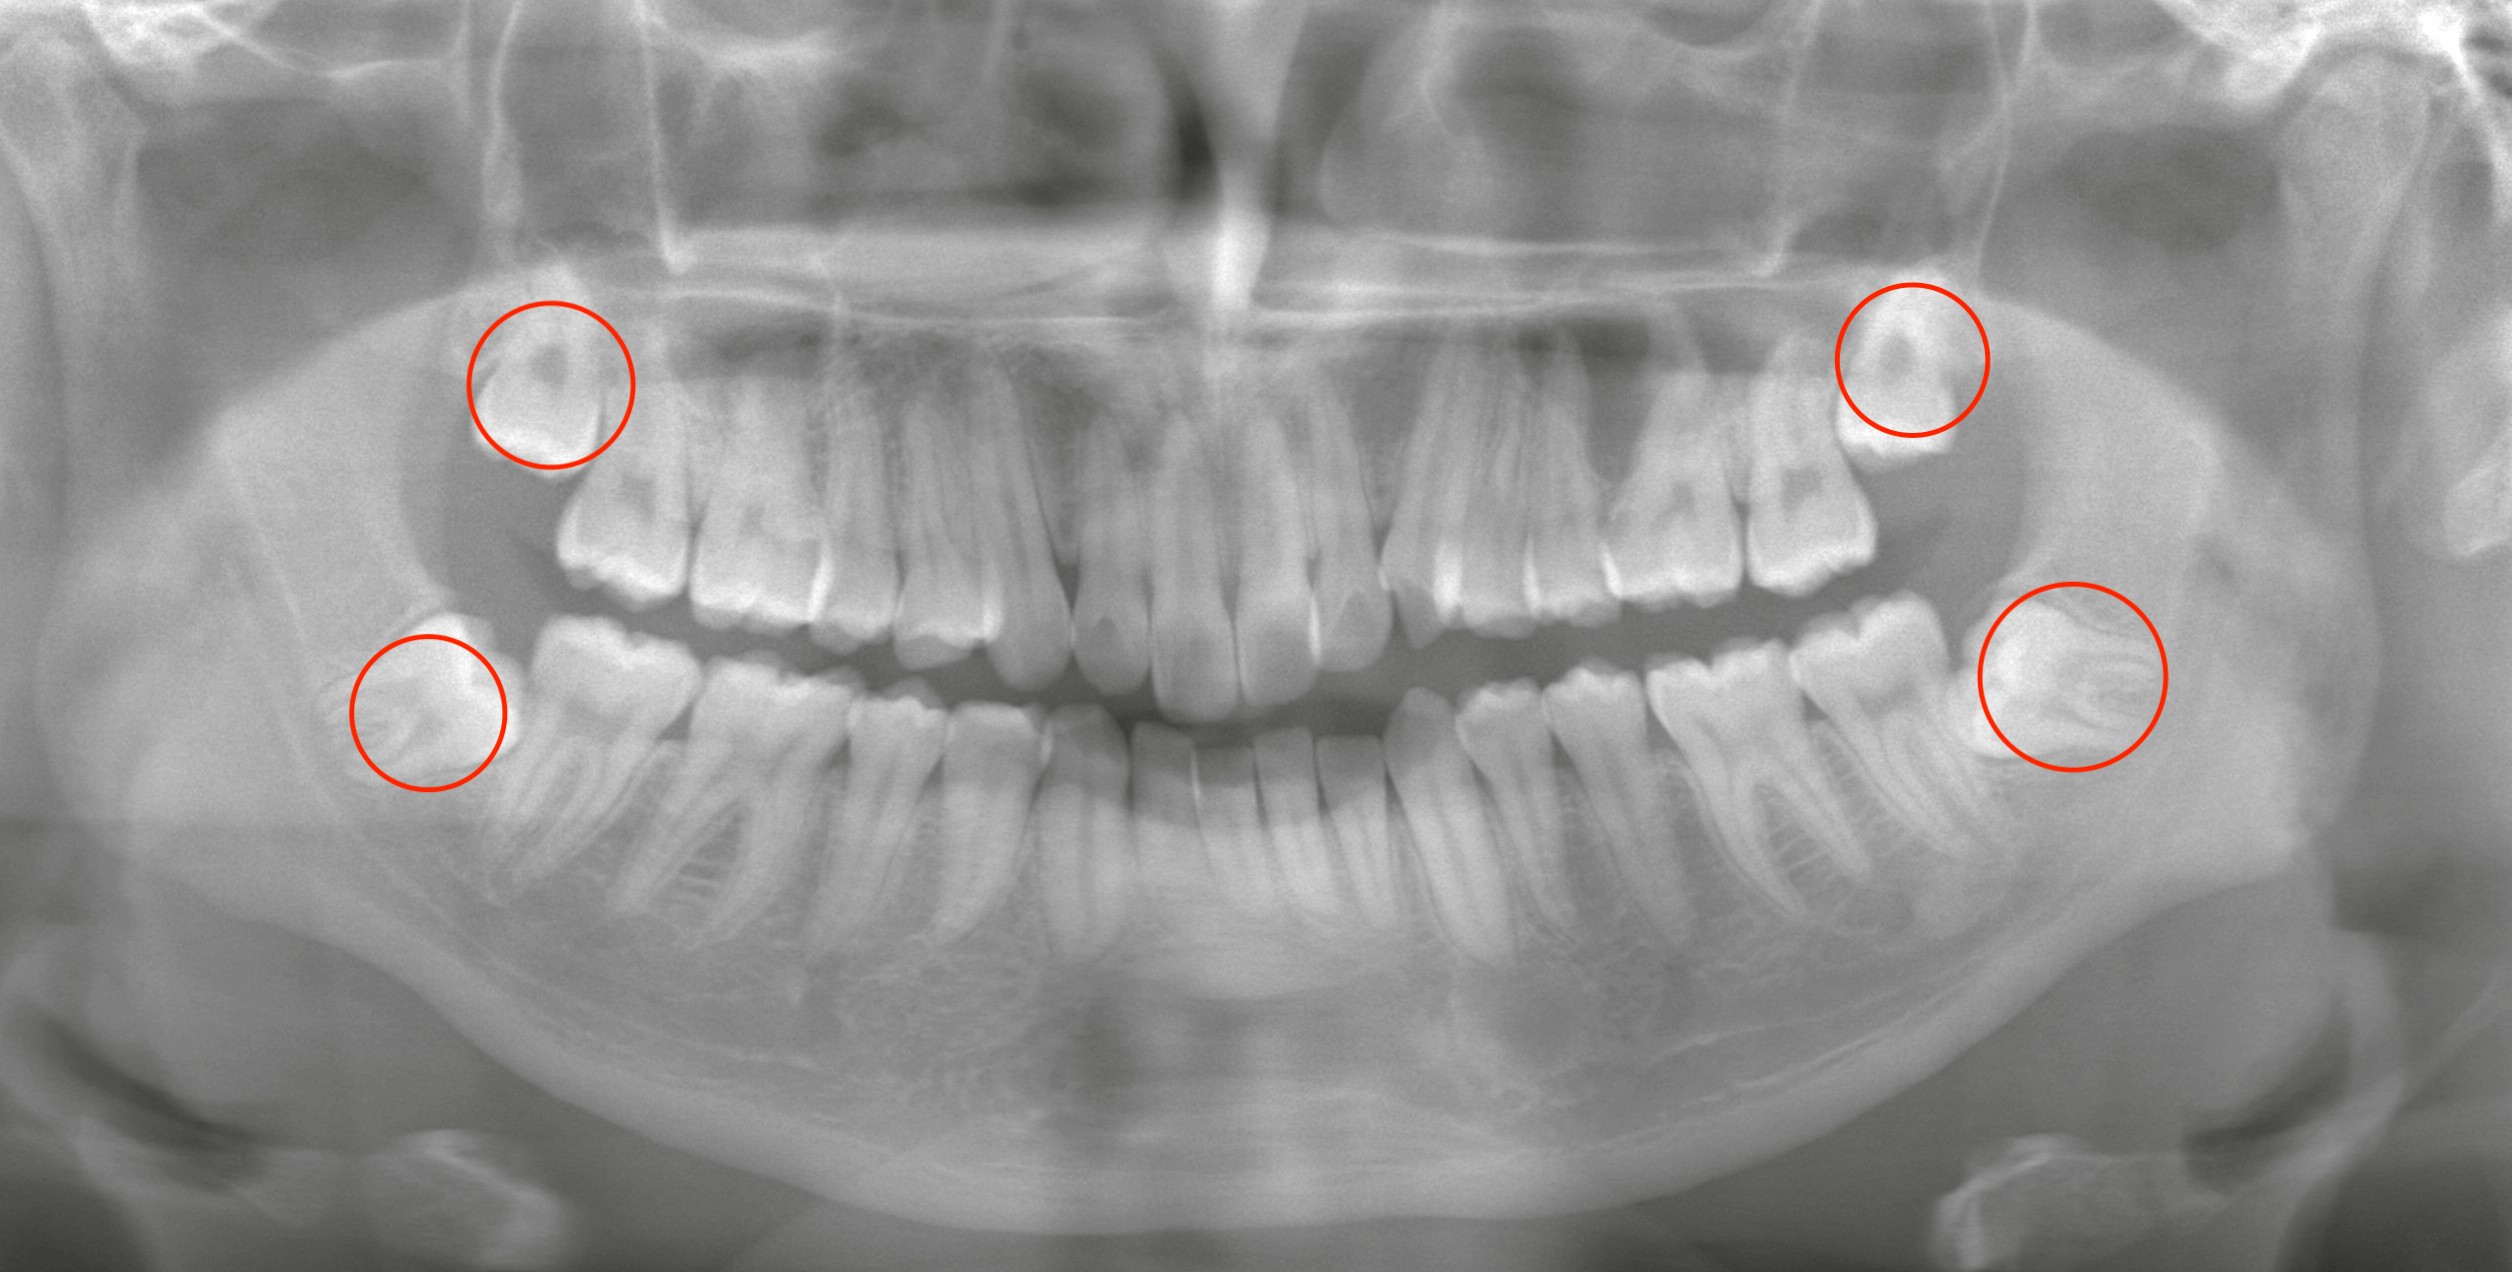

今回のケース:まずは上顎を優先して抜歯

矯正歯科の先生から、

「まずは上顎を優先して抜歯してほしい」

という明確なリクエストがありました。

来院当日、上顎の左右2本の埋伏歯を抜歯。

下顎は次回、左右それぞれ1本ずつ抜歯する計画です。

下顎の親知らずは水平埋伏で、術後の腫脹が比較的強く出やすいタイプ。

さらに稀ではありますが、腫れが喉側に出ると呼吸が苦しくなるリスクもあります。